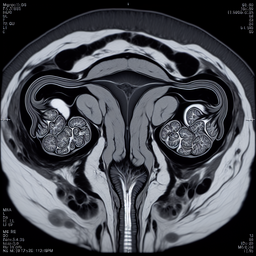

МРТ гістеросальпінгографія прохідності маточних труб

МРТ гістеросальпінгографія – це сучасний метод діагностики, який використовується для оцінки прохідності маткових труб. На відміну від традиційної рентгенівської гістеросальпінгографії, МРТ не використовує іонізуюче випромінювання, що робить її менш навантажувальною для організму.

2. **Проведення**: За допомогою контрастної рідини, введеної в порожнину матки, оцінюється стан маткових труб. Після введення контрасту робиться серія МРТ-знімків.